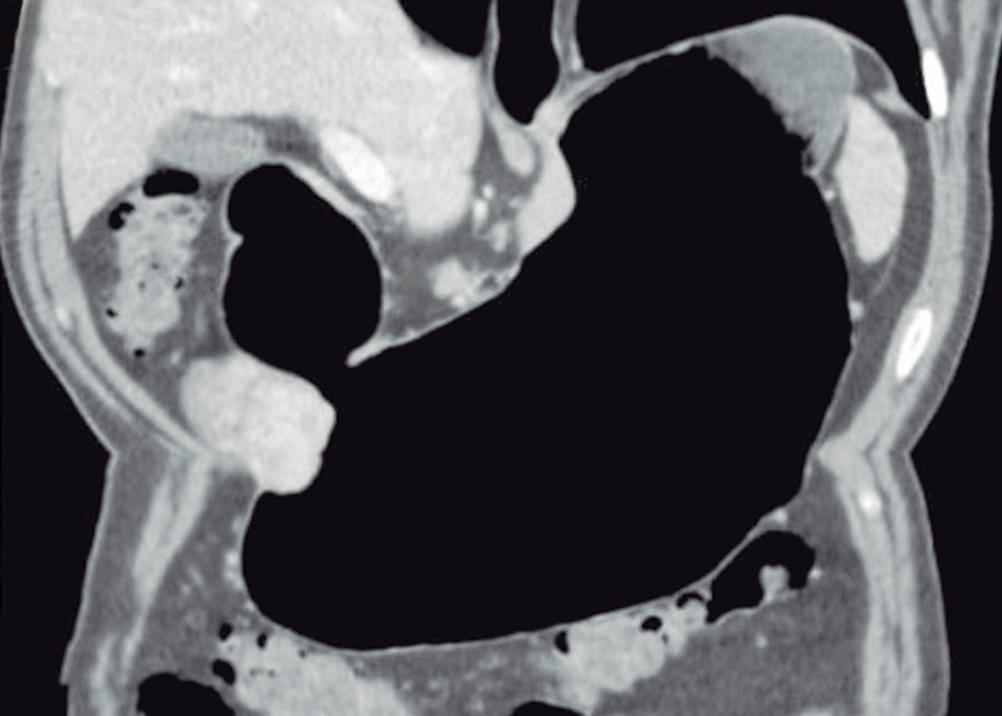

Evaluación de un paciente con dolor epigástrico y hallazgos sincrónicos infrecuentes

Roy López Grove, Daniela Soloaga, Juan Carlos Spina

Roy López Grove, Daniela Soloaga, Juan Carlos Spina 398